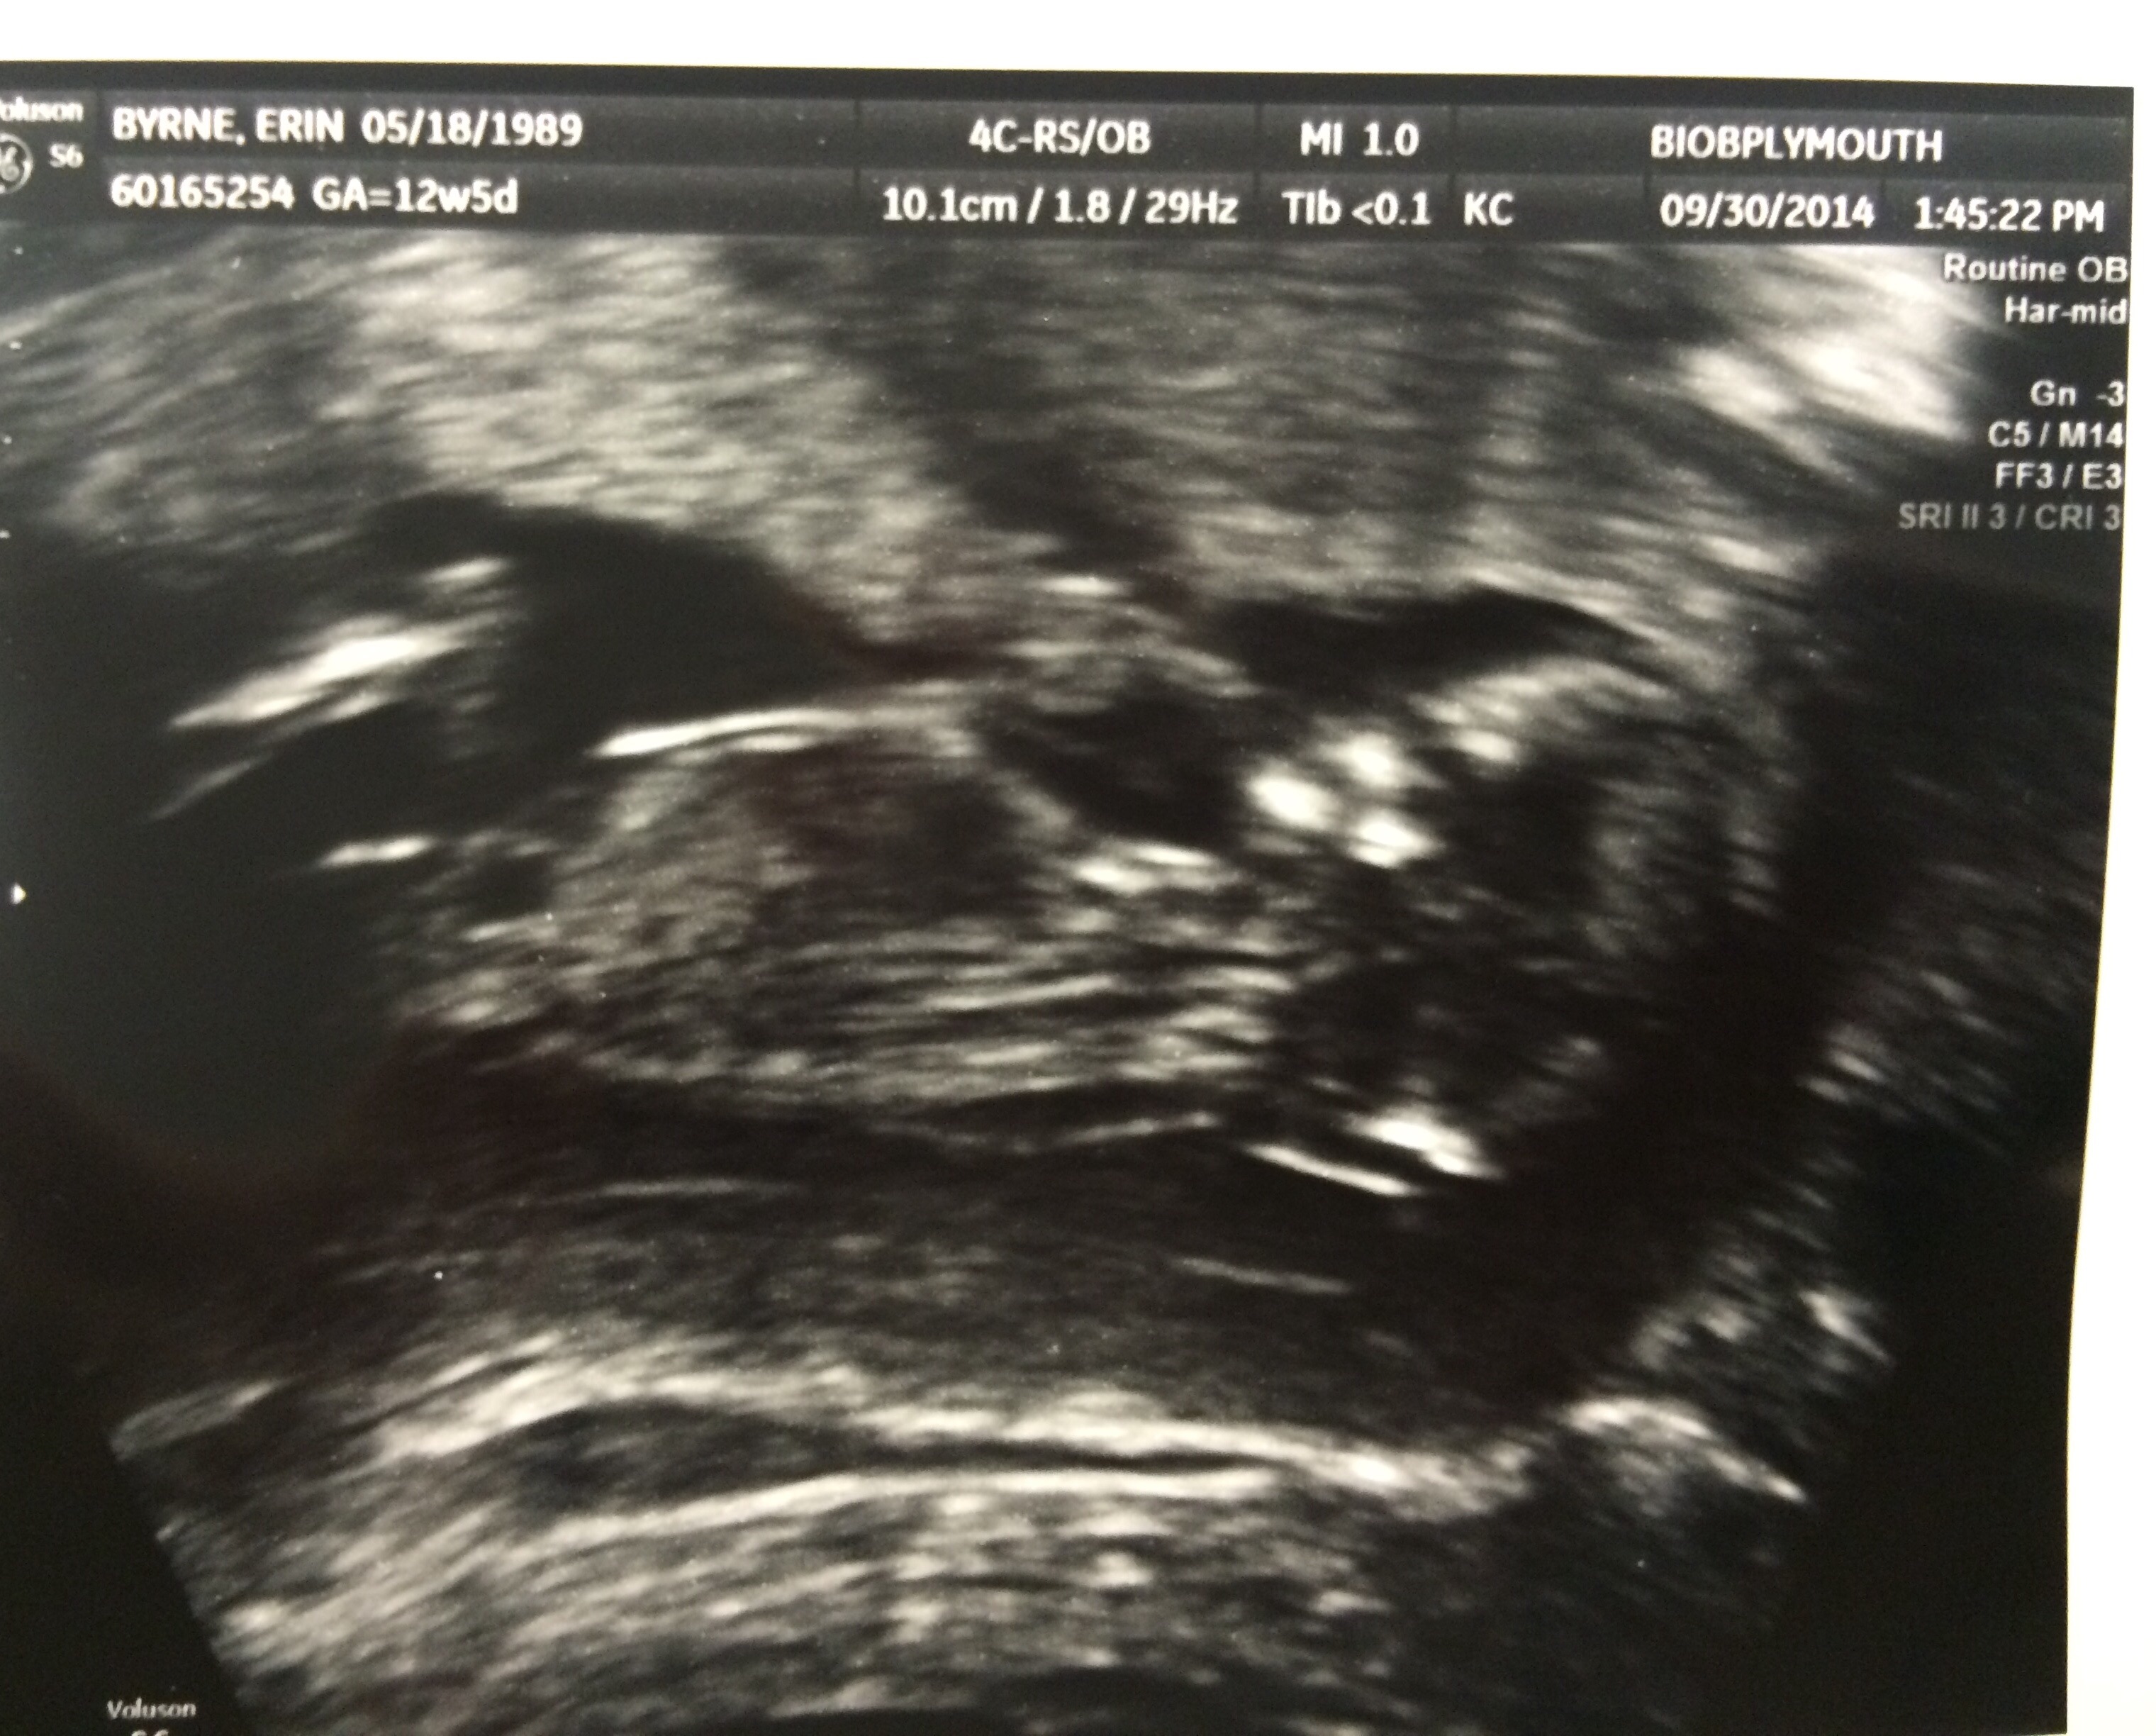

12 weeks 5 days HB 161

Asked the ultrasound tech if she had to guess the sex and she said girl which makes me very excited!!